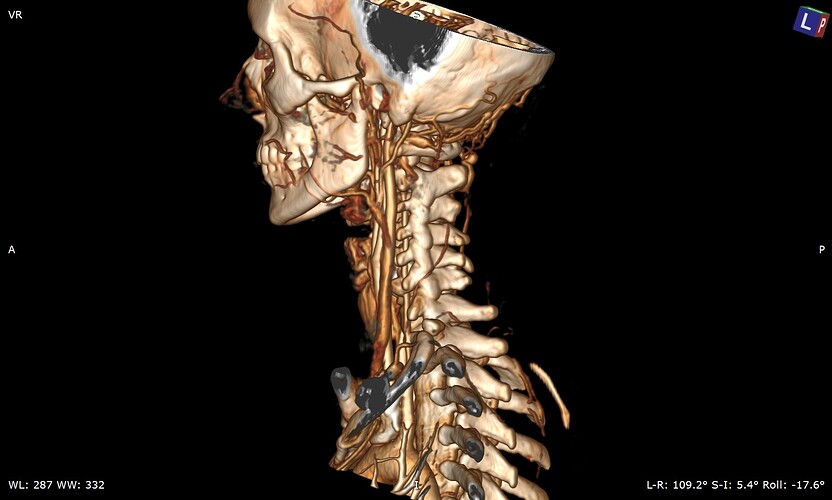

So my daughter had her icp monitoring done two days ago. They kept her at Hopkins until this evening and the results have not been officially given although they said that the fluctuations in her head pressure were not enough to consider it a problem with her csf so that is a good thing. Her pressure did rise significantly whenever she bent over or when her head went below her heart. Now we are left with the real possibility that the pressure has been coming from her jugular vein compression all along. We have a telecall with Dr. Costantino in early March so hopefully he will be able to look at her imaging and confirm that she does have compression at the C1 level. I’m not sure that her styloids are part of the equation but I think it is clear from the imaging that the C1 is involved. I’m going to upload many of her images that I was able to make into 3d with RadiAnt but I’m not sure how good they are. I would appreciate anyone who can view them to give me their opinion on anything they may see that could be causing her head pressure. I did include some 2D images as well because they do seem to show the C1 compression of the jugular.

I’ve annotated a couple of the images you posted & will explain what I see under each image.

On the left side, your daughter’s IJV looks compressed at the styloid/skullbase level, possibly at C1 then lower between C4-C6. Because her cervical spine is so straight, it almost appears the transverse processes of those 3 vertebrae are in contact with her IJV & even below them. She has quite a number of collateral veins in the area of her skull base which is an indication of IJV compression. Though I can’t see the very tip of the greater horn of her hyoid bone on this side, it almost looks like it could be in contact with her external carotid artery (ECA) which can cause different symptoms than the IJVs.

There are very similar situations with the right side though I can’t see enough of the hyoid bone on this side to comment about the right greater horn.

Her compression doesn’t look severe, but since she’s symptomatic, the compression is enough for her body to be reacting to it. That Hopkins confirmed its not high enough to be a problem is good & bad. Good because she’s at lower risk for a CSF leak, but bad because I feel, in some respect, they were saying IH isn’t causing her symptoms which it most likely is.

Her styloids are very wide at the skull base & are not very well defined. I think that’s why her IJVs looked compressed to me right at the styloid/skull base junction, but you’ll need to see what Dr. Costantino thinks.

I agree that her styloids do look pretty chunky at the skull base, so it’s worth seeing what Dr C says, but be prepared for the compression further down to still be an issue? Stenting should be a last resort I felt personally, I’ve been very lucky that my IJVs opened up enough after surgery to resolve the head pressure…